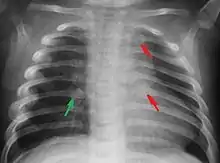

Most nations with child abuse laws deem the deliberate infliction of serious injuries, or actions that place the child at obvious risk of serious injury or death, to be illegal.[36] Bruises, scratches, burns, broken bones, lacerations — as well as repeated "mishaps," and rough treatment that could cause physical injuries — can be physical abuse.[37] Multiple injuries or fractures at different stages of healing can raise suspicion of abuse.

C. Henry Kempe and his colleagues were the first to describe the battered-child syndrome in 1962.[40] The battered-child syndrome is a term used to describe a collection of injuries that young children sustain as a result of repeated physical abuse or neglect.[41][42] These symptoms may include: fractures of bones, multiple soft tissue injuries, subdural hematoma (bleeding in the brain), malnutrition, and poor skin hygiene.[42][43]

Physical

The immediate physical effects of abuse or neglect can be relatively minor (bruises or cuts) or severe (broken bones, hemorrhage, death). Certain injuries, such as rib fractures or femoral fractures in infants that are not yet walking, may increase suspicion of child physical abuse, although such injuries are only seen in a fraction of children suffering physical abuse.[90][91] Cigarette burns or scald injuries may also prompt evaluation for child physical abuse.[92]